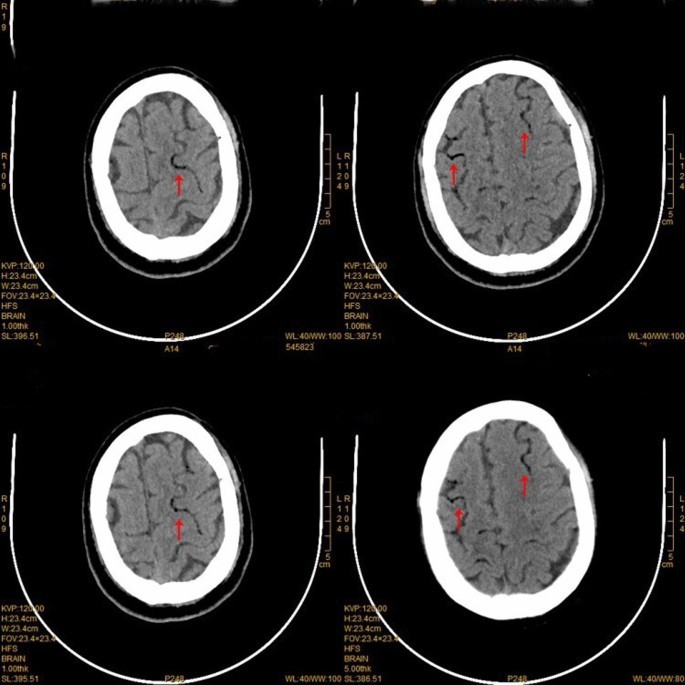

General anesthesia was induced and maintained according to standard protocols during surgical preparation. Then right pneumonectomy was performed, and the surgical incision was located at the posterolateral side of the fourth intercostal space. The pulmonary artery, pulmonary vein and bronchus were cut off with a stapler, with intraoperative bleeding of about 100 ml. After the operation, the thoracic drainage tube was clamped, and the patient returned to the ward after waking up. Three hours after the operation was completed, the patient suddenly lost consciousness while sitting in bed chatting with his wife. The patient’s blood pressure was low (76/53 mmHg), and the indexes of heart rate, respiration and oxygen saturation were normal. After opening the thoracic drainage tube, a small amount of tension gas and 200 ml of bloody fluid was discharged. We immediately performed CT examination and excluded brain lesions. CT examination showed that there was a large amount of gas in the tissue space between the chest and neck (Fig. 2). Blood clots accumulated in the thoracic cavity, and CT angiography showed no abnormalities in the major cerebral arteries (Fig. 3). However, multiple free air can be seen in the blood vessels of bilateral frontal sulcus (Fig. 4). In addition to free air, suspicious cerebral infarction was also seen in the right occipital lobe (Fig. 5). It is presumed that air entering the cerebral circulation led to air embolism. The patient had seizures soon after the CT scan, manifesting as binocular gaze and tremor of limbs. Then the patient was quickly transferred to ICU. Respiratory assistance, mannitol dehydration and empiric antibiotic treatment were used after ICU transfer. 800 ml pleural fluid was drained from the thoracic cavity 6 h after the operation, and a second thoracotomy was performed to stop bleeding. Then blood clot was removed from the thoracic cavity. After the operation, the patient was sent back to the ICU for ventilator-assisted breathing, and the head was protected by mild hypothermia using an ice blanket to prevent excessive brain damage. At the same time, mannitol dehydration was used to reduce brain edema and anti-infection treatment was carried out. On the next day, the brain CT showed a significant decrease of air in the brain (Fig. 6). There was no significant increase in cerebral infarction lesions compared with the first day. After 3 days of ventilator-assisted breathing, the patient’s condition gradually improved. On the third day after air embolism, the brain CT was reexamined. There were patchy low density areas in bilateral thalamic basal ganglia, temporal lobe and occipital lobe, which was cerebral infarction lesions. The patient was discharged after 25 days of treatment after cerebral infarction. He was conscious at the time of discharge, with neurological impairment symptoms of bilateral in which symptoms of left limb are more serious. The process from onset to recovery was smooth. After 3 months of follow-up, most of the neurological deficit symptoms had been recovered except for the left upper limb (Fig. 7).